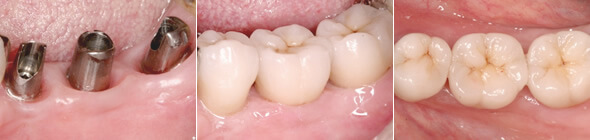

治療①

オールセラミッククラウンを装着。天然歯と見分けが付かない色調。

治療例

期間 3ヶ月~1年 9~12回

内容 失った部位にインプラントを埋入

歯肉骨増生を行い天然歯を削らずに修復

費用(税別) ¥400,000~¥500,000

治療②

オールセラミック、ジルコニアで自然感のある状態に修復。奥歯でしっかり噛めるようになりました。

大臼歯2本をインプラントに

大臼歯2本をインプラント。小臼歯1本も同時に修復。

土台をインプラントに固定

ジルコニアの土台をインプラントに固定。

自然感のある状態に修復

期間 7回

内容 欠損にインプラントを2本埋入し修復